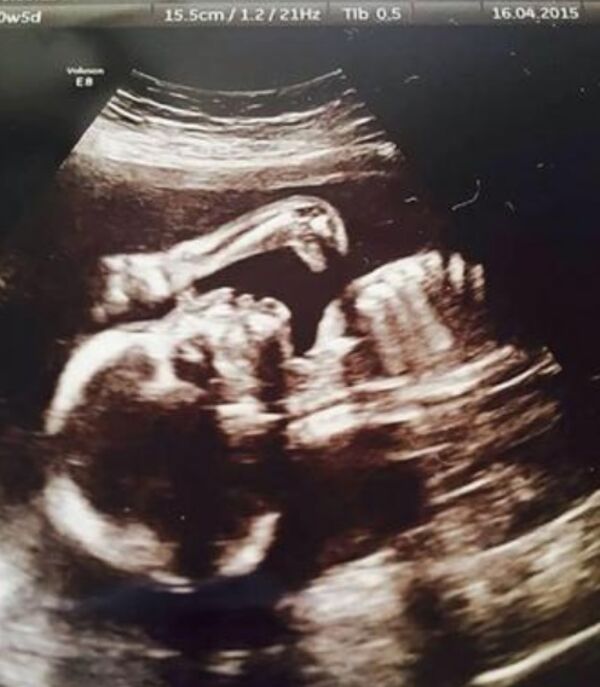

Bebekler anne karnında ne yapar?